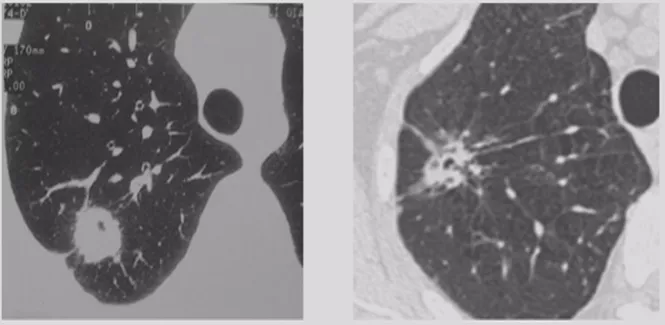

非手术活检的局限性

但是非手术活检获取的标本都是小标本,所以取标本有限。如果病理报告基于针尖大小的组织样本,那就存在许多不确定性。上图所示,是我们的一个病例,4月21日,外院CT引导下经皮肺穿刺,我院病理会诊为慢性炎症;5月16日入院,我建议再做一次活检,于是5月19日经皮肺穿刺,病理提示还是慢性炎症;两次病理提示均为慢性炎症,但是完全用慢性炎症解释这个肺结节还有些疑问,我建议再做一次经皮肺穿刺,6月7日第三次活检的病理结果提示为中分化腺癌,而且基因检测提示ALK阳性,是黄金突变,靶向治疗效果很好。因此,我们取小标本的时候,要慎重解释阴性结果。